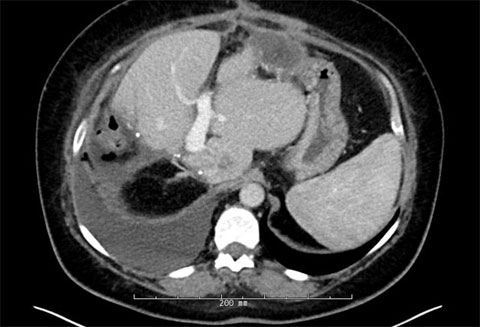

Post-second-surgery MRIs

The patient had a successful percutaneous embolization of the right portal vein and transjugular embolization of the right hepatic vein.

Four weeks later, the patient came in for the second stage of the procedure, the right hepatectomy.

The patient had adequate growth in the liver remnant and was brought back for the removal of the right lobe of her liver where we removed approximately 70% of her liver, leaving 30% of it behind.